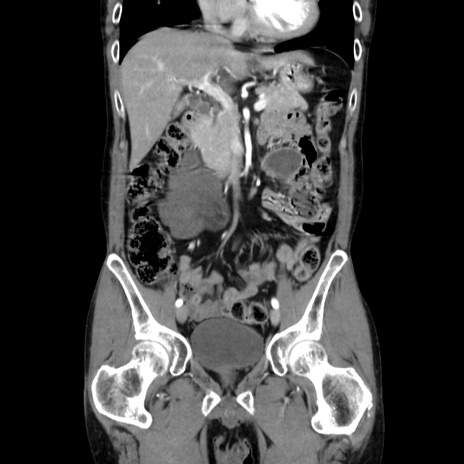

症例37(冠状断像)

【症例】40歳代 男性

【主訴】腹痛

【現病歴】4時間ほど前に電車に乗車中に臍部上より腹痛出現。徐々に増悪し起立困難となり、救急外来受診。生ものは数日食べていない。今朝お雑煮を食べた。

【身体所見】BT 36.8℃、BP 117/84mmHg、HR 91/min、SpO2 97%、苦悶様、腹部:臍上部広範囲圧痛あり、反跳痛±

【データ】WBC 8100、CRP 0.03